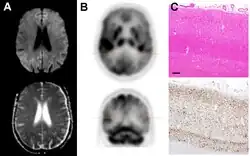

Brain FDG PET-CT tends to be markedly abnormal, and is increasingly used in the investigation of dementias.

- Patients with CJD will normally have hypometabolism on FDG PET.[55]

Imaging of the brain may be performed during medical evaluation, both to rule out other causes and to obtain supportive evidence for diagnosis. Imaging findings are variable in their appearance and also variable in sensitivity and specificity.[49] While imaging plays a lesser role in diagnosis of CJD,[50] characteristic findings on brain MRI in some cases may precede onset of clinical manifestations.[51]

Histopathology

Testing of tissue remains the most definitive way of confirming the diagnosis of CJD, although even a biopsy is not always conclusive.[56]

In one-third of people with sporadic CJD, deposits of "prion protein (scrapie)", PrPSc, can be found in the skeletal muscle or the spleen.[57] Diagnosis of vCJD can be supported by biopsy of the tonsils, which harbor significant amounts of PrPSc; however, biopsy of brain tissue is the definitive diagnostic test for all other forms of prion disease. Due to its invasiveness, a biopsy will not be done if clinical suspicion is sufficiently high or low. A negative biopsy does not rule out CJD, since it may predominate in a specific part of the brain.[58]